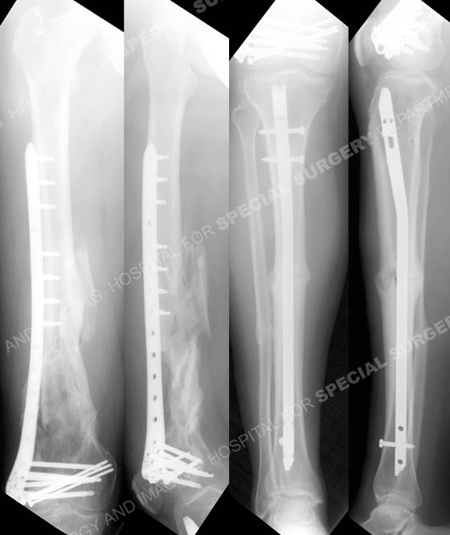

Anteroposterior and lateral femur and tibia radiographs at 1 year illustrating healed distal femur and tibia fractures in excellent alignment.